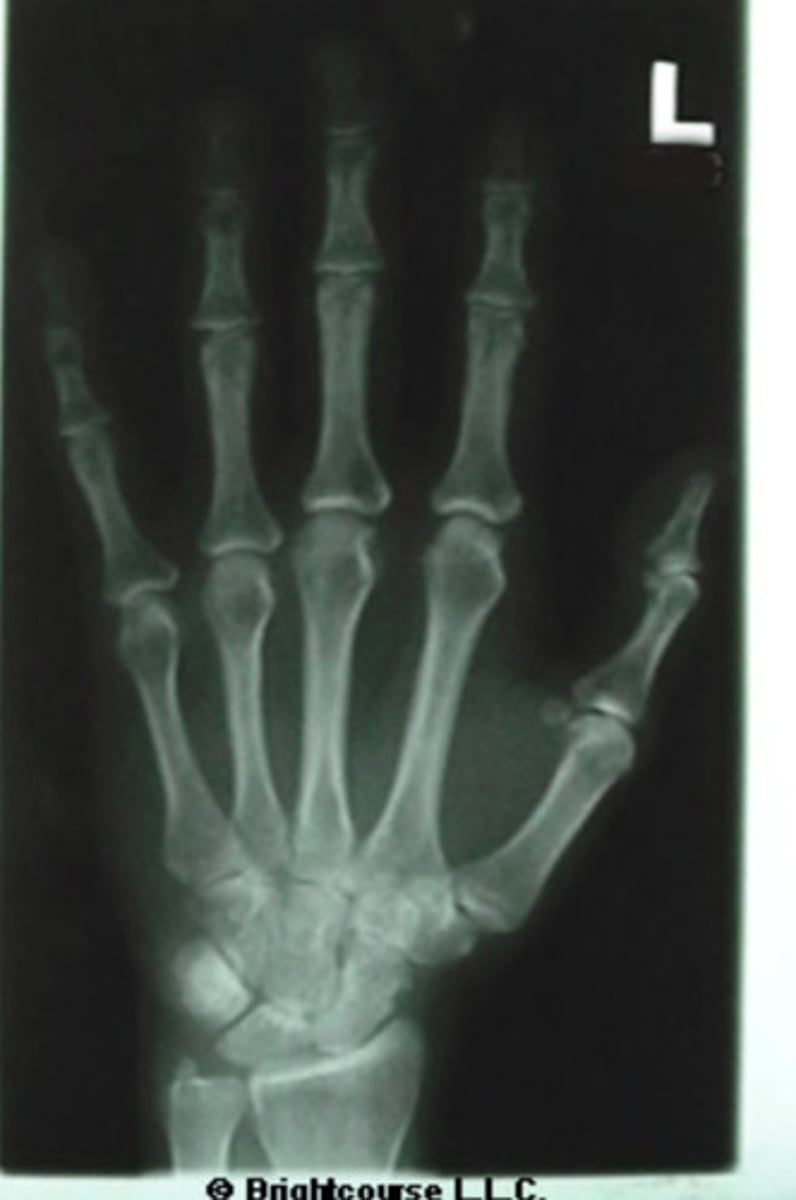

PA Hand

What is name of the radiographic projection?

Metacarpophalangeal joint

What structure is indicated by number 9?

Distal interphalangeal joint

What structure is indicated by number 7?

Shaft of 3rd metacarpal

What structure is indicated by number 5?

Base of the 3rd metacarpal

What structure is indicated by number 6?